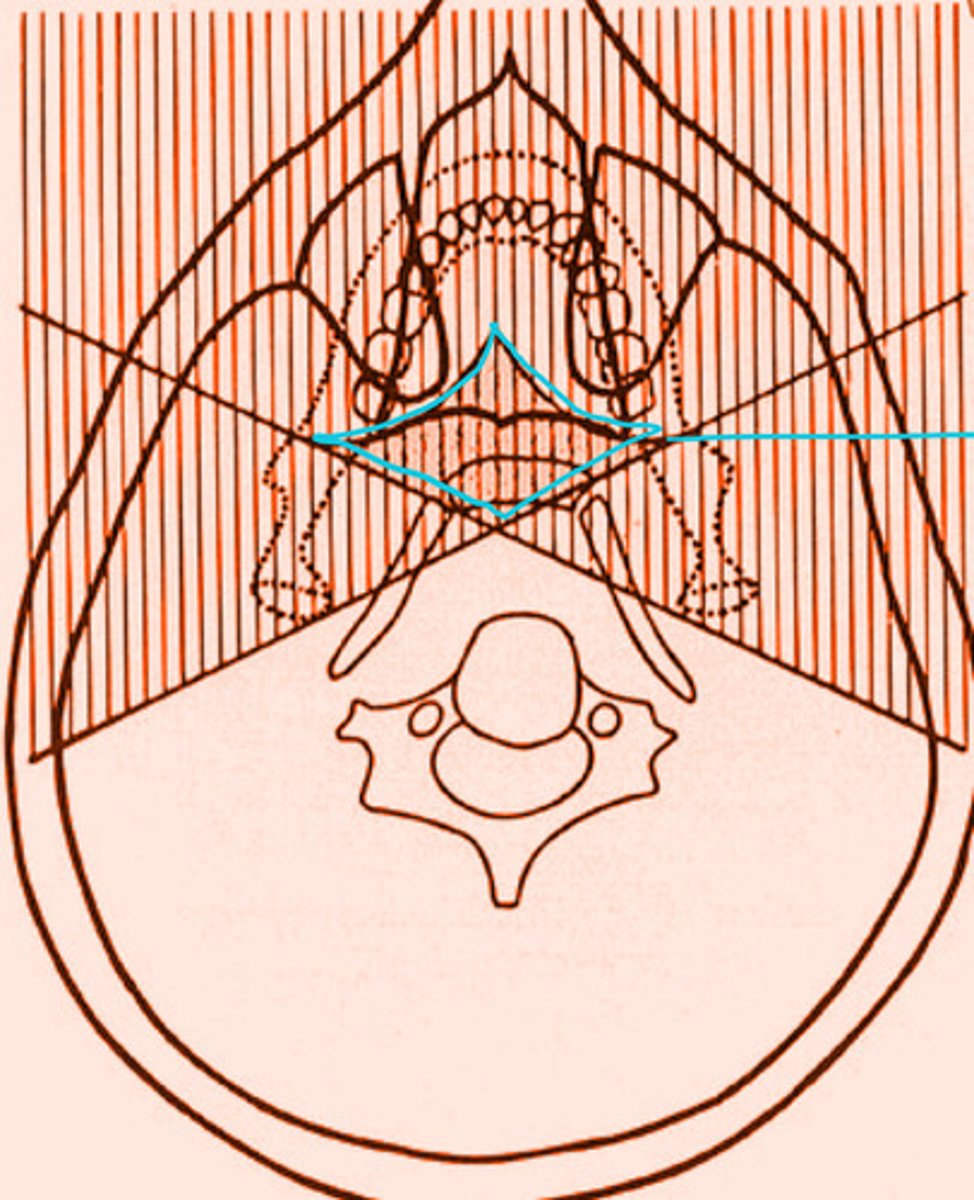

the shaded regions will produce what type of images?

real and double image

the shaded region within the blue diamond will produce a total of __ images

3

the shaded region within the blue diamond will produce a total of 3 images. What types of images are they?

2 real

1 ghost